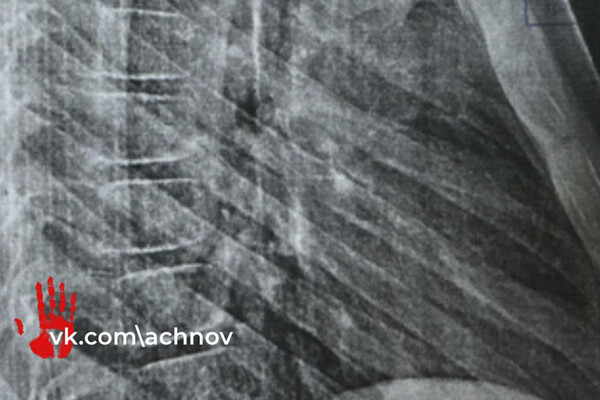

Все происходило без согласия родителей несовершеннолетних. Один из детей упал и сильно ударился, в больнице у него диагностировали перелом грудной клетки и ушибы.